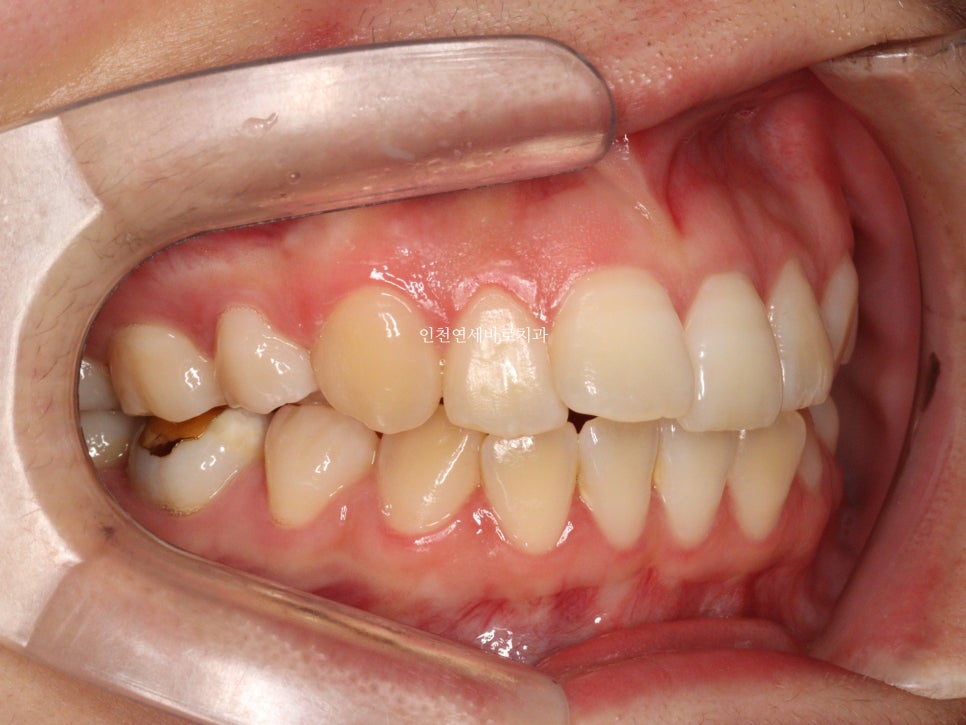

오늘은 교정이 끝난지 오래되어 재교정을 하고 싶어 내원했던 환자분 이야기 입니다.

예전에 중학생때 발치교정치료를 받았다고 합니다.

환자분의 나이는 이제 30대

약 15년만에 다시 교정치료를 결심하셨다고 합니다.

결혼을 앞둔 분이었고

앞니하나가 많이 틀어졌는데 점점 틀어진다고 하셨습니다.

철사 유지장치를 붙여놨었는데 오래전에 탈락 하고 다시 붙이지 않으셨다고 합니다.

변화모습입니다.

장치의 제작이 한달이나 걸리기 때문에 3/30이 처음 교정치료를 시작했던 날입니다.

약 3개월의 변화모습입니다.